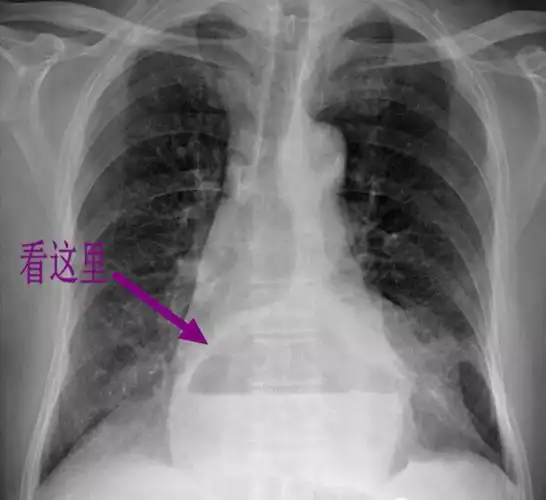

食管裂孔疝_手机搜狐网

经典影像之食管裂孔疝 - 好大夫在线